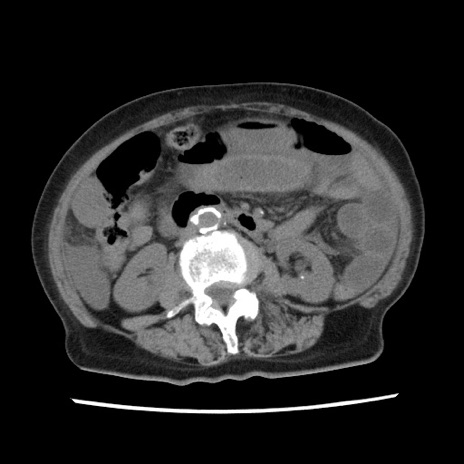

冠状断像

矢状断像